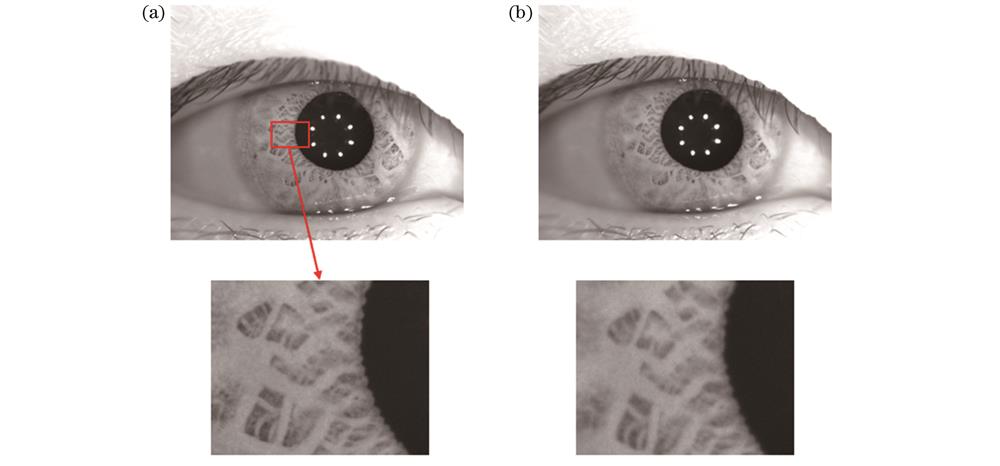

图 4. 采集的人眼图像与ROI图像。(a)人眼原图像;(b)瞳孔ROI图像

Fig. 4. Collected image of human eye and ROI image. (a) Original image of human eye; (b) ROI image of pupil

感兴趣区域提取前后的灰度分布如

图 11. 人眼离焦图像序列4中部分图像。(a)序列第8幅图像;(b)序列第9幅图像

Fig. 11. Partial images of sequence 4 in human eye defocused image. (a) 8th image of sequence; (b) 9th image of sequence